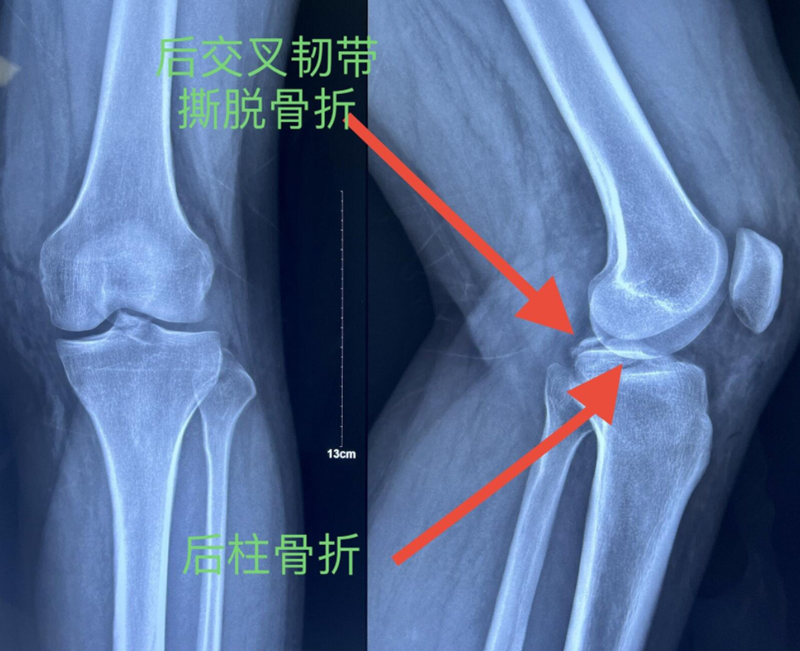

x男,30岁,体重100kg,在五楼擦玻璃时坠落到四楼致伤2天。

诊断:左胫骨平台后柱骨折,后交叉韧带撕脱骨折,左踝关节pilon骨折3型。

术前影像学资料:

图7 前交叉韧带撕脱骨折与平台后柱骨折